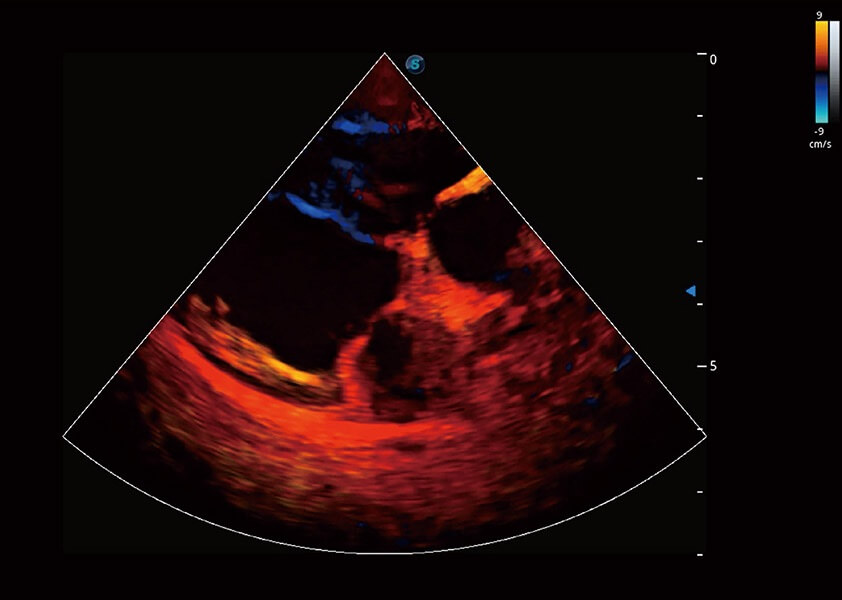

ProPet 60 作为一款高端台式动物超声设备,为动物医生的日常诊断提供了一系列贴合动物临床需求、解决临床实际问题的高级成像功能。凭借全系列高清探头,满足医生对腹部、心脏、生殖、浅表、肌骨等成像的所有需求,切实帮助您提升检查效率,提高诊断信心。

兽用彩色多普勒超声诊断系统

动物是人类最亲密的朋友和最值得信赖的伙伴。1xBET也一直致力于探索动物专用的超声影像解决方案。 全新推出的ProPet系列,是1xBET在动物超声影像智能化、专业化、精准化的一次跨越式革新。动物不能用言语来表述自己的不适,通过超声影像,ProPet系列搭建了动物医生与不同物种沟通的“桥梁”,为动物医生注入了“治愈之力”。